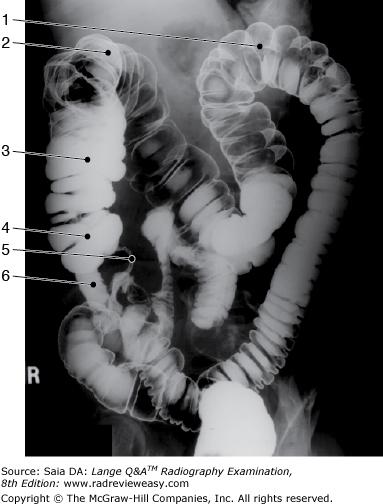

The structure indicated by the number 2 in Figure 6–11 is the

A ascending colon.

B descending colon.

C transverse colon.

D sigmoid colon.

-The figure shown is a double-contrast BE, oblique position. Since the left colic/splenic flexure (number 1) is “open,” this is either a RPO or LAO position. Also demonstrated are the descending colon (number 2), and transverse colon (number 3). Barium has refluxed into the ileum (number 5).